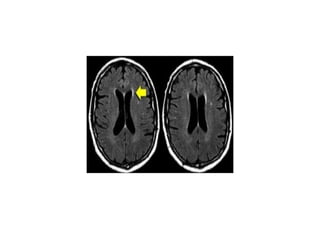

• TYpical findings for MS as seen

in this case are:

• Multiple lesions adjacent to

the ventricles (red arrow).

• Ovoid lesions perpendicular to

the ventricles (yellow arrow).

• Multiple lesions in brainstem

and cerebellum.

• These ovoid lesions are also

called Dawson fingers.

perpendicular to the

ventricles.

DAWSON FINGERS

the ventricles (Dawson fingers).

• Enhancing lesion.

• Multiple lesions adjacent to the

• Dawson fingers are typical for

MS and are the result of

inflammation around

penetrating venules.

These veins are perpendicular